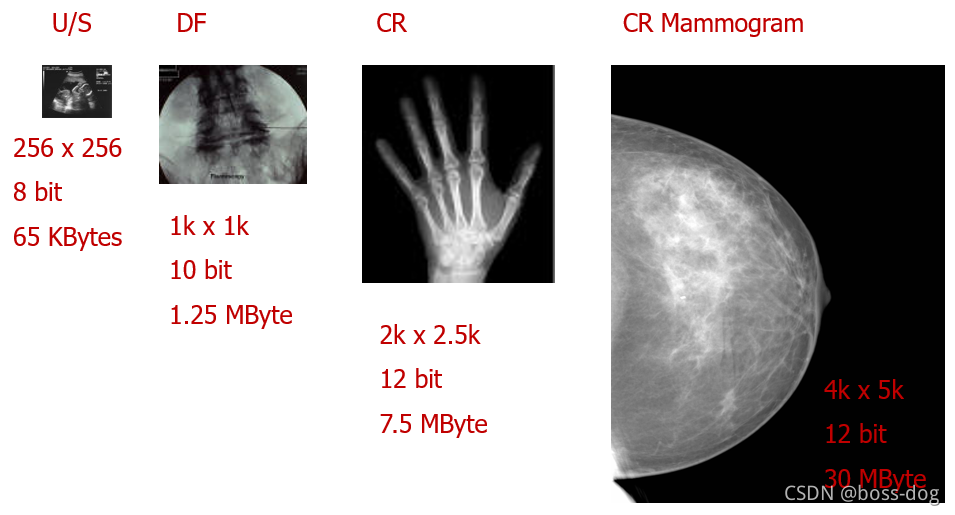

图像质量:分辨率和存储大小

彩色的/单色的

-

图像尺寸x号的图片